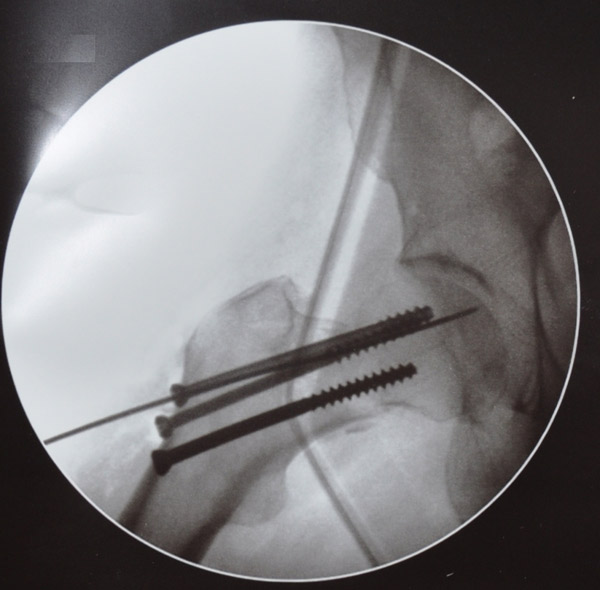

С  2009г  начали  выполнять  протезирование  тазобедренного  сустава  однополюсными  гемипротезами.  Широко  используется  накостный  остеосинтез,  интрамедулярный  остеосинтез  с  блокированием,  чрезкостный остеосинтез  (ЧКОС).

Выполнено 116 операций тотального эндопротезирования тазобедренных суставов.

На  2011г.  по  ВМП  запланировано около  200  операций по тотальному эндопротезированию  тазобедренного  сустава.